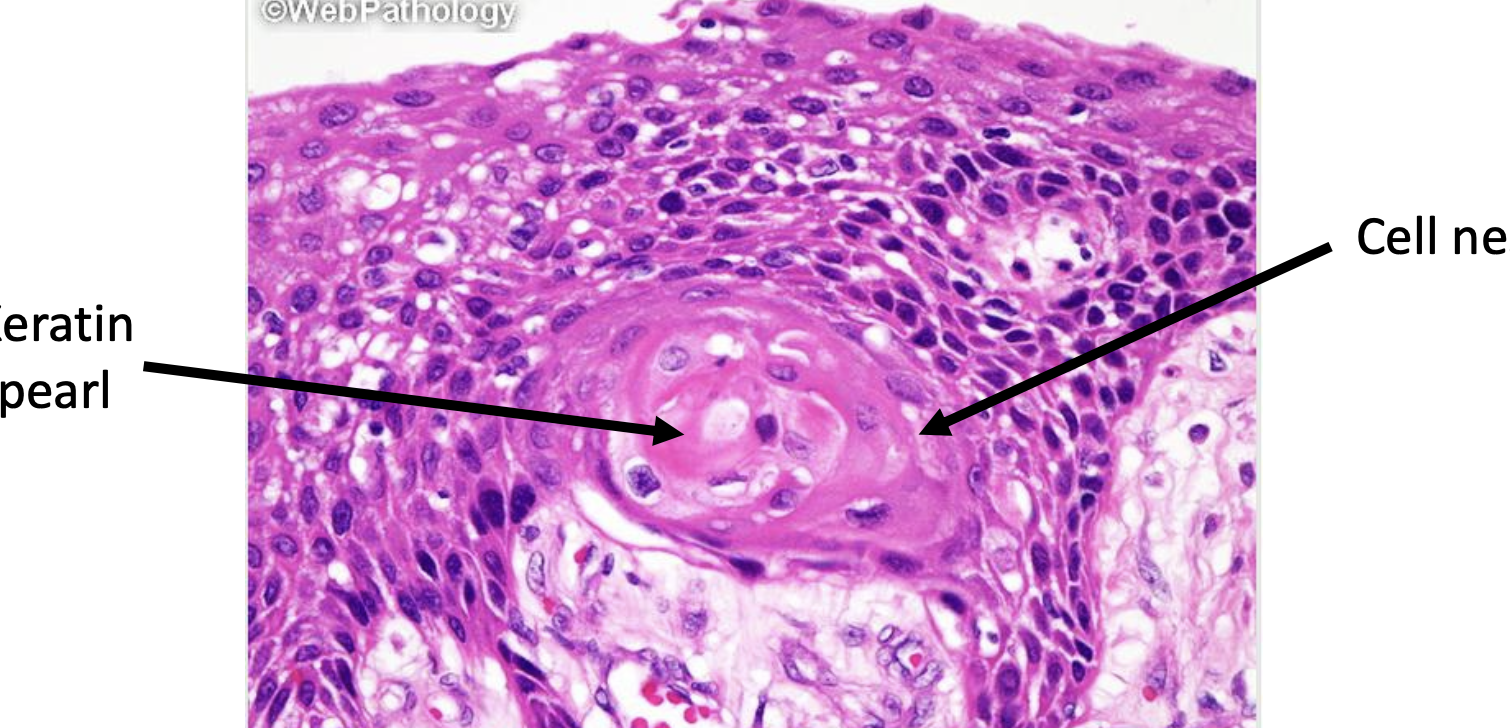

Additionally in well differentiated SCCs malignant tumour cells are arranged in groups called cell nests with central keratinization called keratin pearls or whorls

Another feature of SCC is intercellular bridges (dunno if they are uses ad brindges they just look like perpindicular strands) (click on image for magnification)